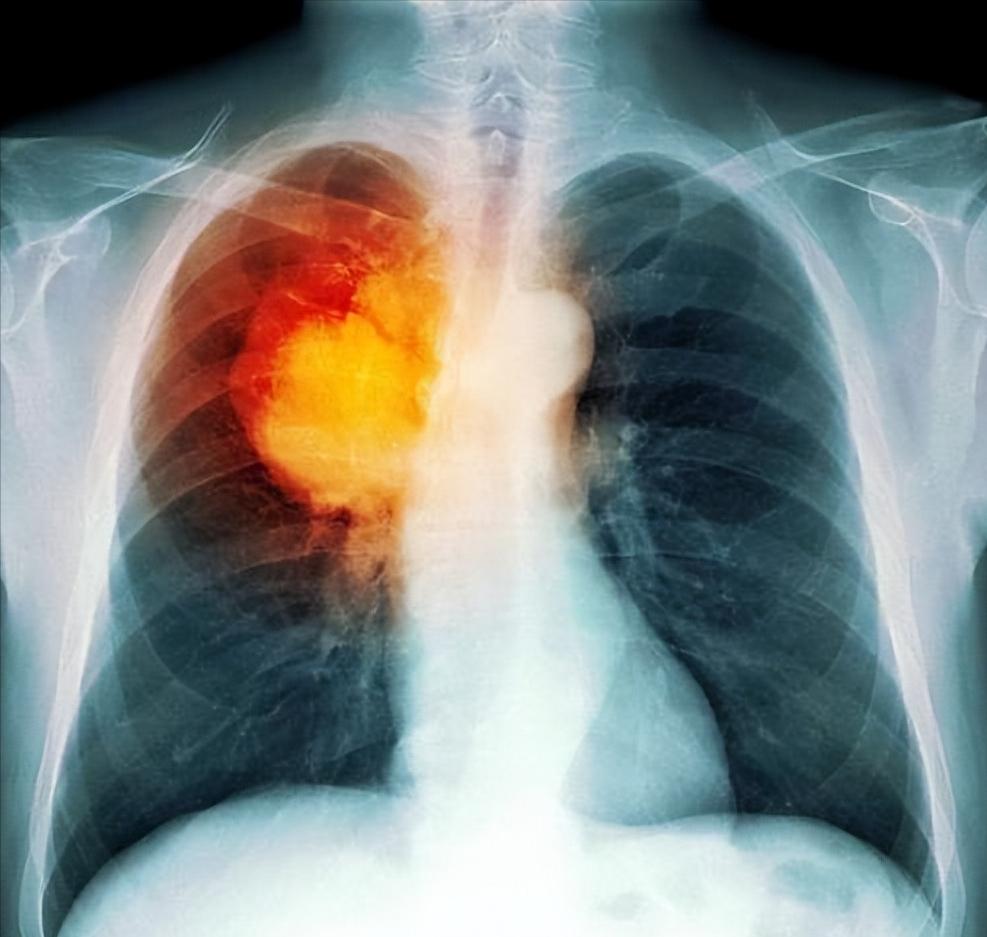

连续咳嗽了两个月,总以为是“熬夜上火”,直到一次剧烈胸痛送进了急诊。CT一出,肺部有个3厘米的阴影——肺癌晚期。

肺癌,这个全球每年夺走180万人生命的“沉默杀手”,正悄悄潜入我们身边。但今天,我想告诉你一个更关键的事实:如果能在早期发现,5年生存率能从15%飙升到80%以上! 别被“癌症”二字吓住——它不是命运的判决书,而是我们能主动干预的健康警报。

关键点:治疗效果与发现时机直接挂钩!早期患者5年生存率超80%,而晚期仅15%——早发现1年,生存率多20%。这不是理论,是无数患者用生命换来的真相。